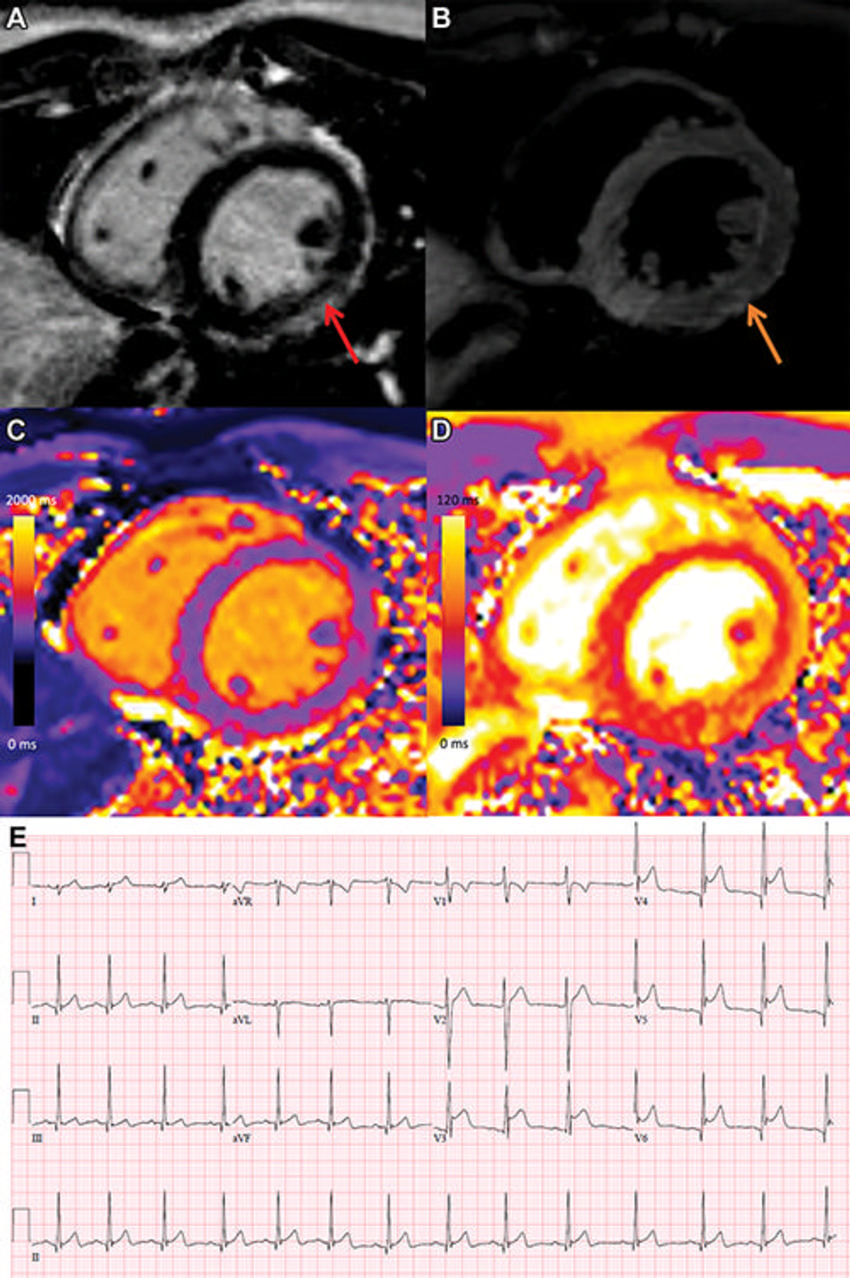

Figure 2. COVID-19 vaccine associated myocarditis. Short-axis 1.5T MRI images and ECG findings of a 19-year-old man with myopericarditis who presented with chest pain 3 days following the second dose of an mRNA COVID-19 vaccine (mRNA-1273). Cardiac MRI performed 2 days after symptom onset demonstrates mid wall to subepicardial late gadolinium enhancement (LGE) at the basal to mid inferior lateral wall with adjacent pericardial enhancement (A, red arrow), corresponding hyperintensity on T2-weighted imaging (B, orange arrows), abnormal high native T1 (C, 1095 ms, maximum region of interest), and abnormal high native T2 (D, 57 ms, maximum region of interest). The ECG demonstrates diffuse concave upward ST segment elevation except in leads aVR and V1, upright T waves in the leads with ST segment elevation, and PR depression, consistent with pericarditis (E). Peak high sensitivity troponin-I was 5772 pg/mL. He was admitted to hospital and was discharged after two days following complete resolution of his symptoms. At short-interval follow-up he was asymptomatic with normal troponin levels.